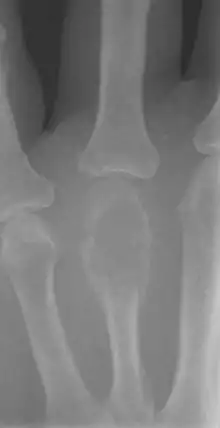

| Non-ossifying fibroma of tibia | |